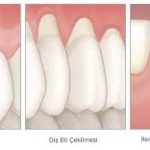

Diş Eti Çekilmesi: Nedenleri, Mekanizmaları ve Önleme Yöntemler Diş eti çekilmesi (gingival retraksiyon), dişeti dokusunun diş kökünden geri çekilmesiyle karakterizedir. Bu durum yalnızca estetik sorun yaratmakla kalmaz, aynı zamanda diş kökünün açığa çıkması nedeniyle hipersensitivite, çürük riski ve periodontal hastalık progresyonu gibi komplikasyonlara yol açabilir. Çekilmenin oluşumunda hem mekanik hem de biyolojik faktörler rol oynar.

2.1 Periodontal hastalıklar

- Diş plakları ve tartar (diş taşı) birikimi, gingivitis ve periodontitise yol açar.

- Gingivitis: Sadece dişetinde inflamasyon vardır, başlangıç aşamasında genellikle çekilme görülmez.

- Periodontitis: Dişeti ve alveolar kemiğin kaybına yol açan ileri inflamasyon, diş eti çekilmesinin en yaygın biyolojik nedenidir.

- Periodontal cep oluşumu ve kemik kaybı, dişetinin diş kökü üzerinden geri çekilmesini kolaylaştırır.